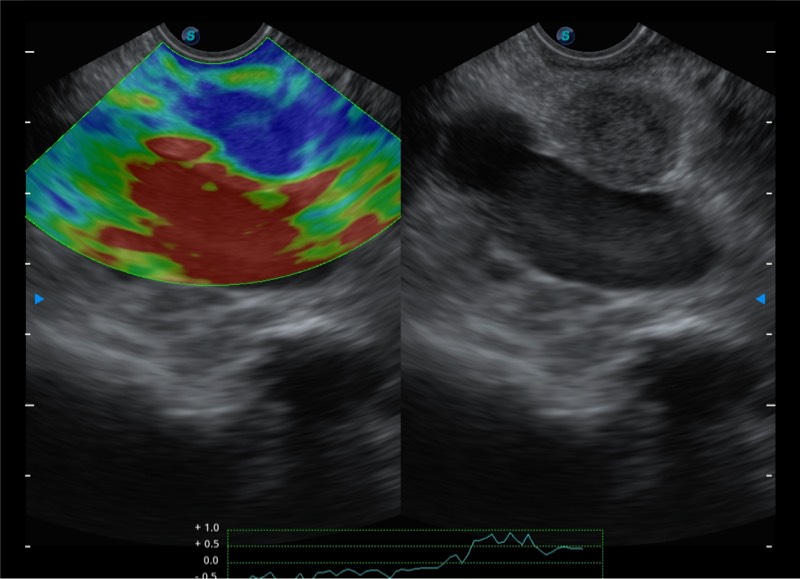

搭载百万级CMOS成像技术

及自主研发凸阵换能器,

可呈现优质的内镜和超声画面

基于二十年的超声技术积累,诸侯快讯官网提供了最新一代的独立超声主机,在提供高质量图像的同时满足多学科使用。具备常见多普勒技术并提供弹性成像、声学造影等高端影像技术。新一代传感器具有更强的抗干扰能力并减少图像伪影。

4-12MHZ宽频输出